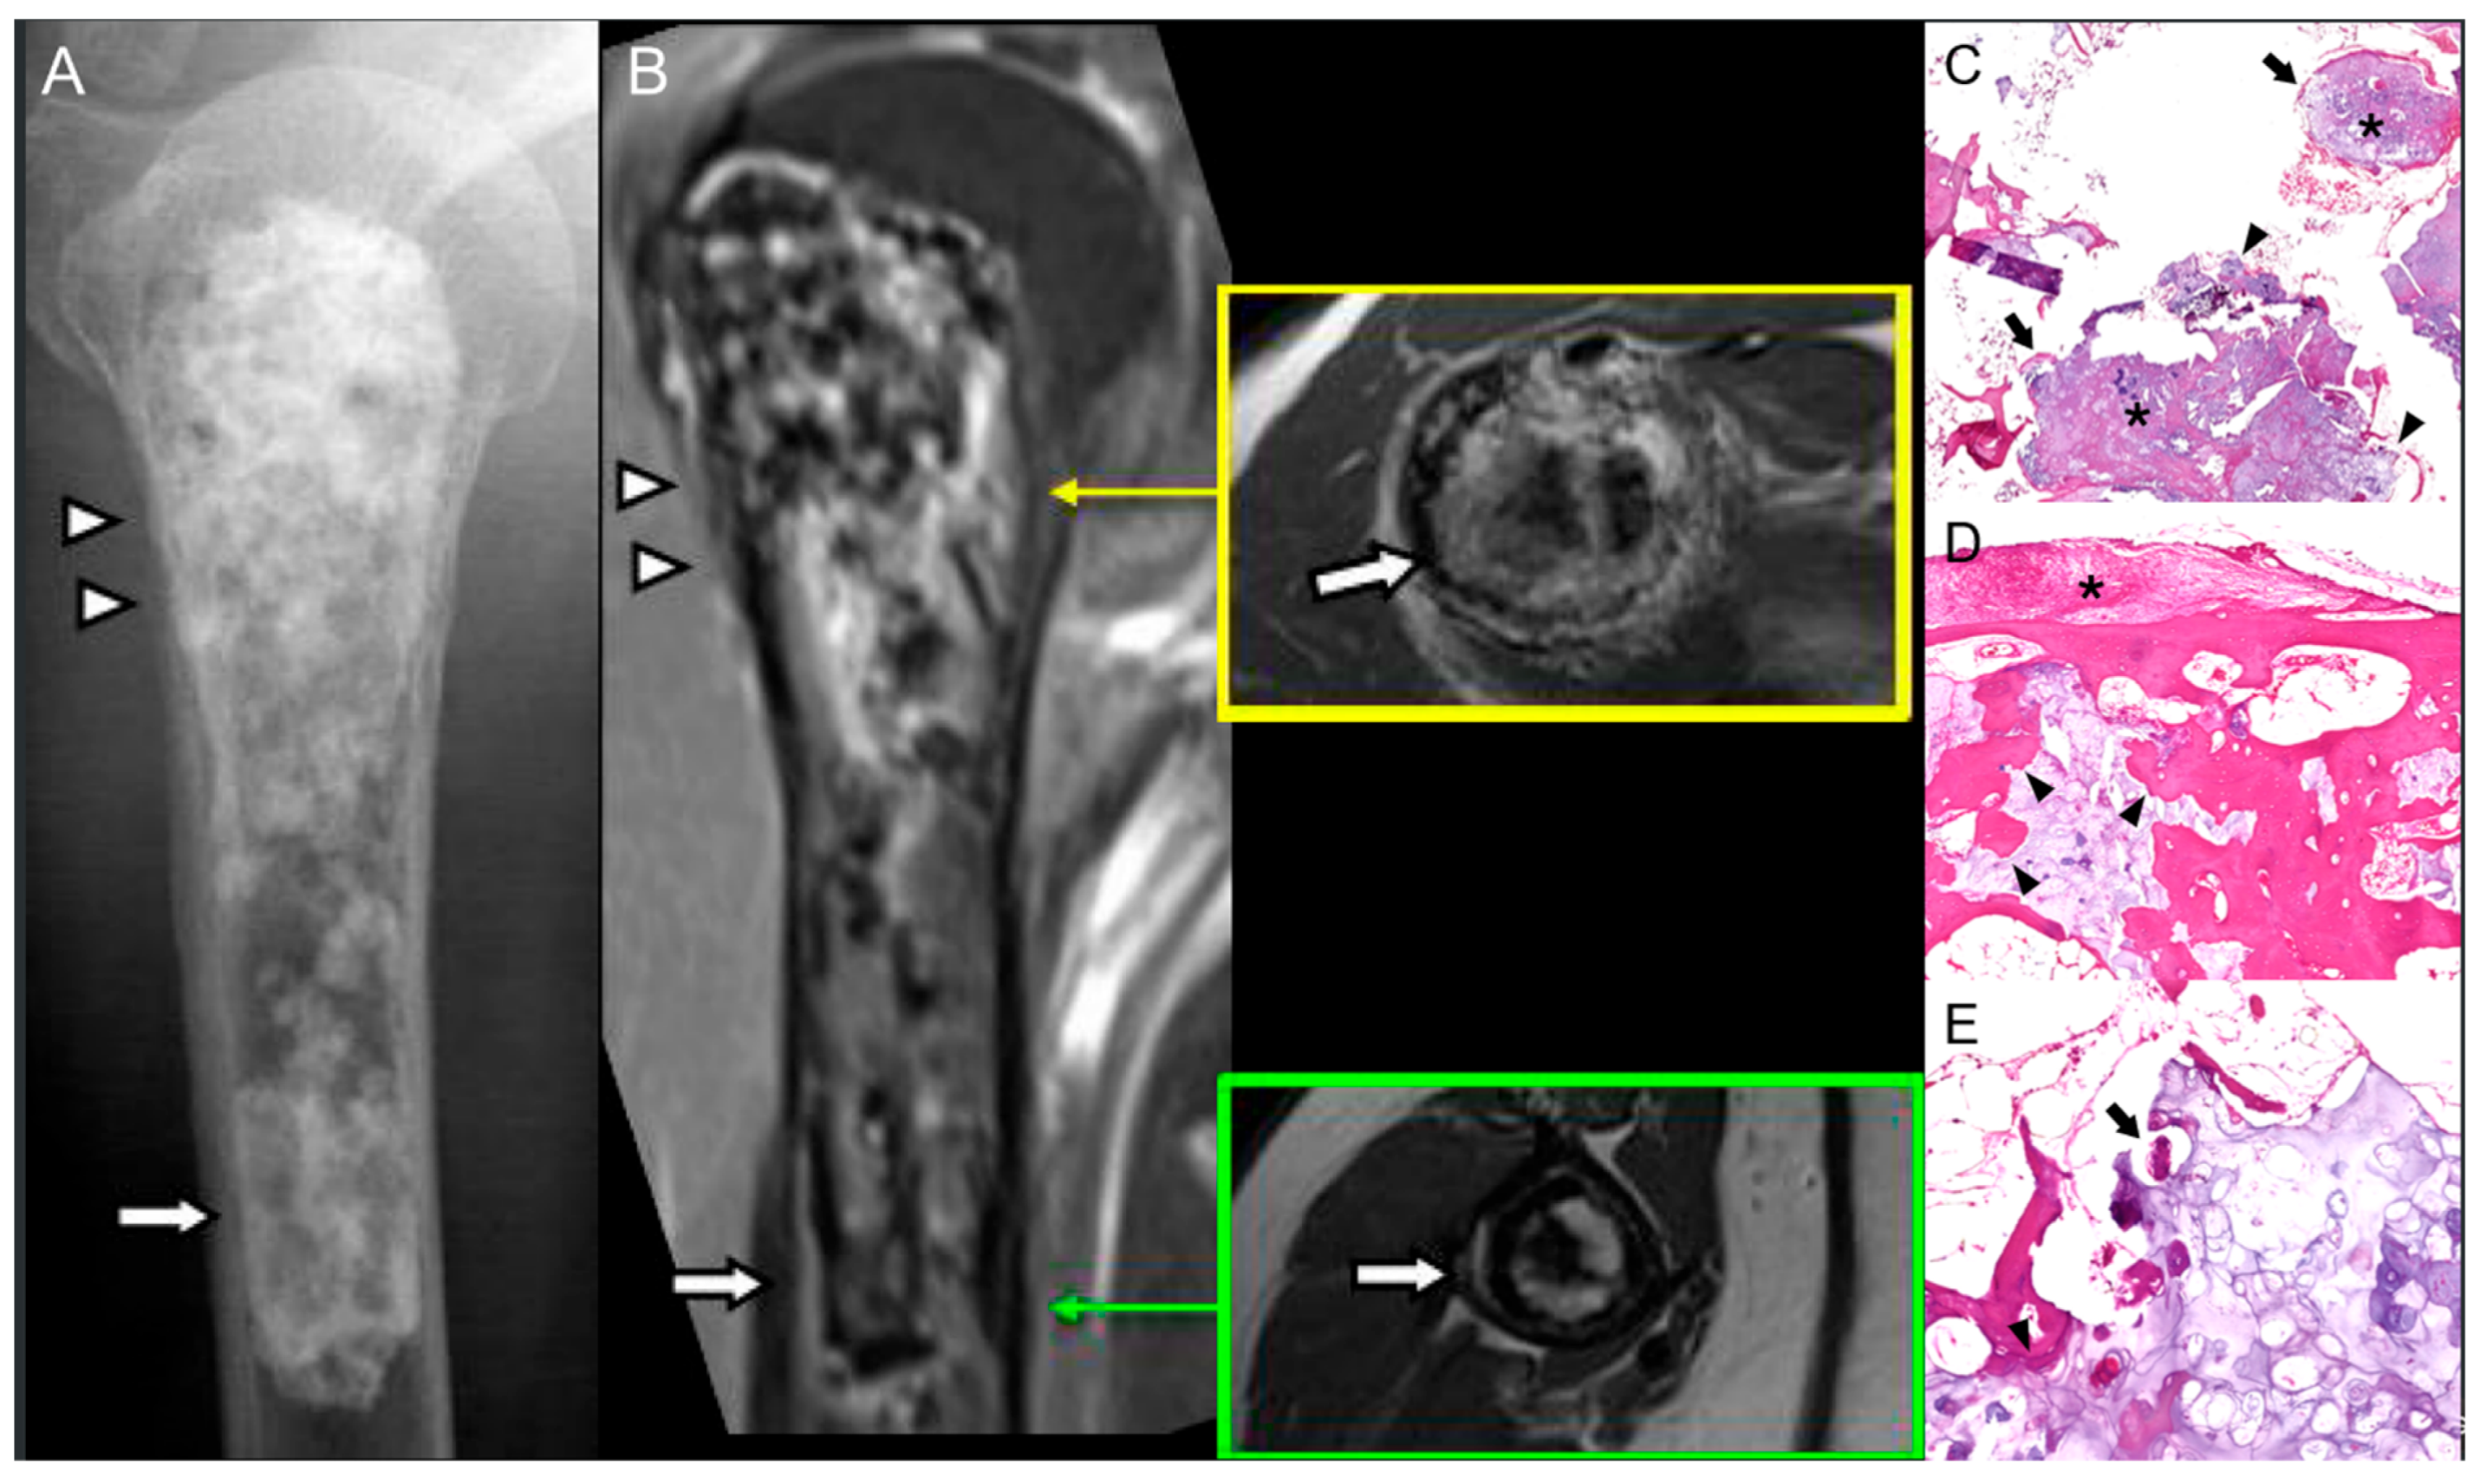

4.1. Low-Grade Central Osteosarcoma